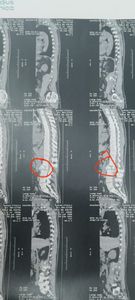

Em 31 de dez de 23, tive um desmaio na de véspera de réveillon onde eu fraturei a coluna. E de lá para cá eu tive mais dois desmaios, uma sequência de crise de pânico devido ao trauma, e um dia tive crise dirigindo, fui socorrido por amigos e familiares, onde eu perdi completamente o sentido cheguei até a pensar que estava perdendo a faculdades mentais. Em janeiro comecei a investigar e descobri que estava com a fratura na coluna através de uma tomografia conforme imagens anexas, que fui ajudado por um anjo da guarda pois eu não tinha um centavo naquele momento. O negócio local tinha parado, eu não estava conseguindo fazer as refeições (marmitas), pois não conseguia ficar em pé.